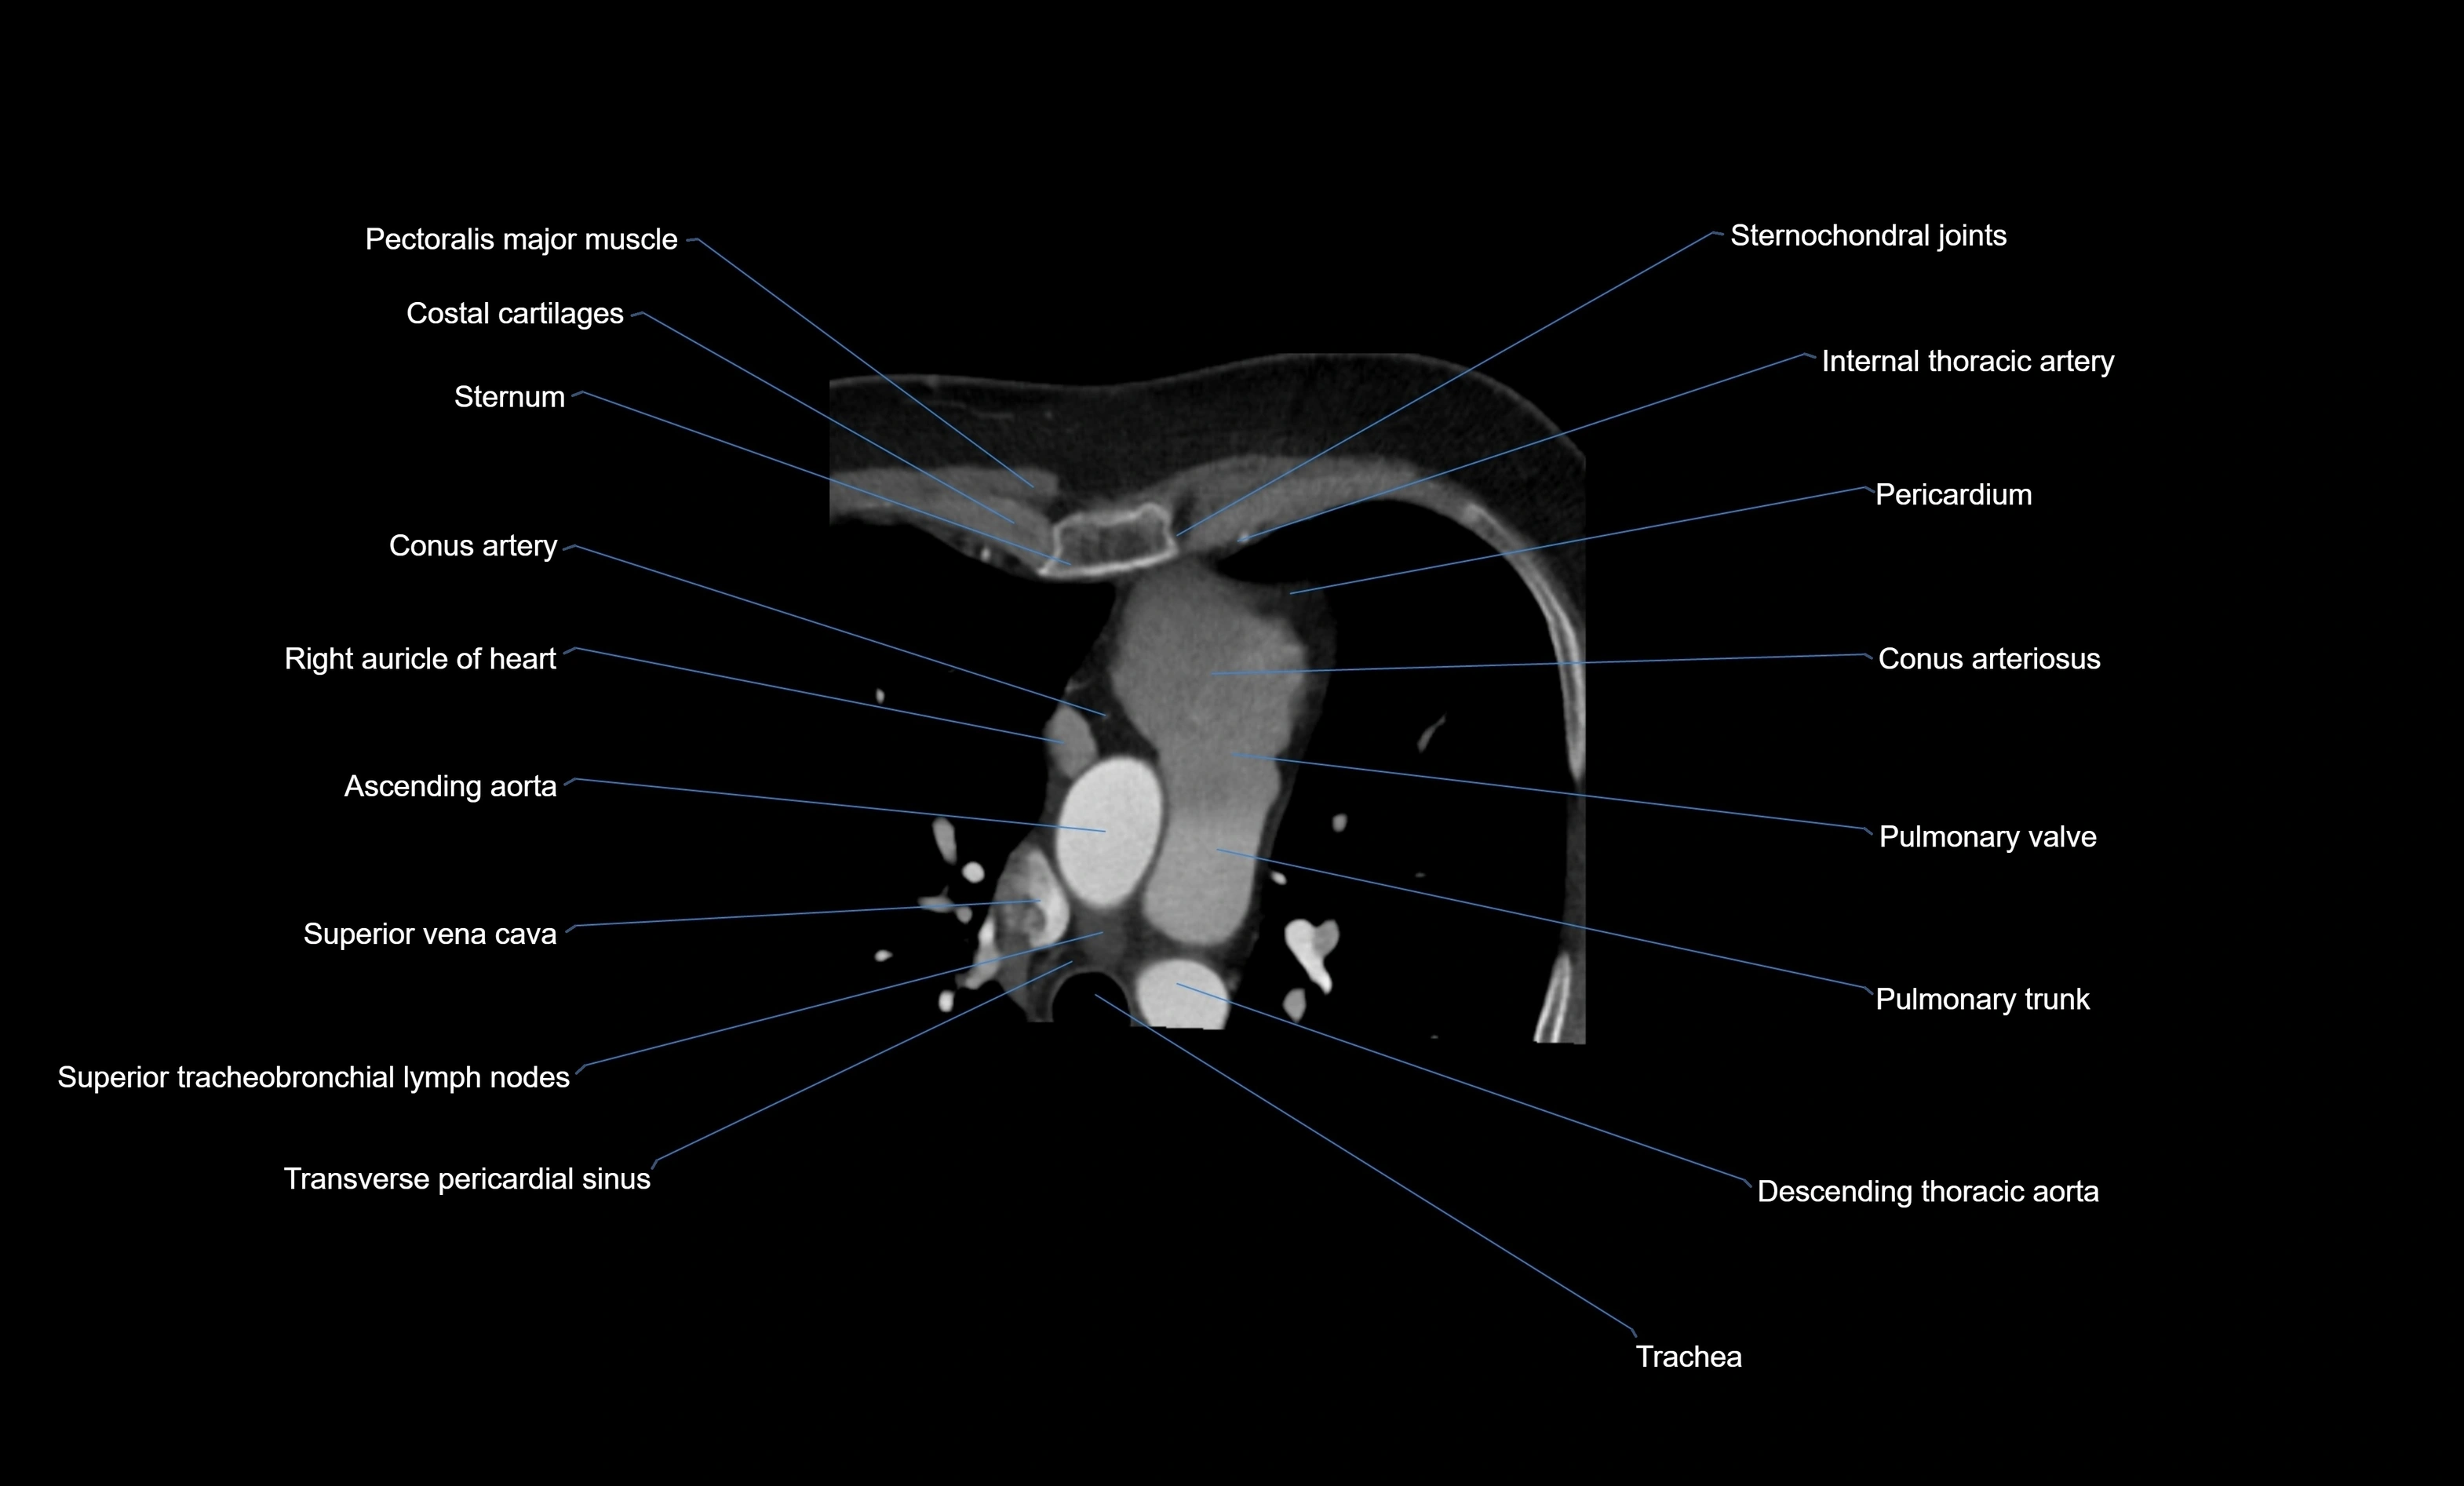

CT images